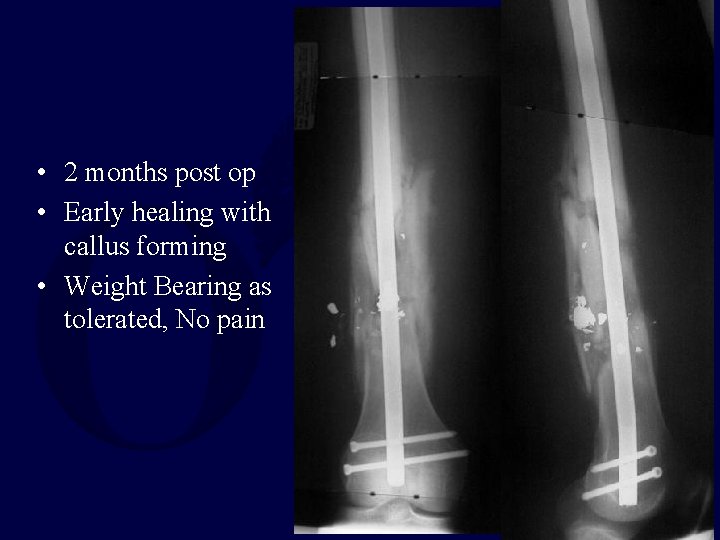

• 2 months post op • Early healing with callus forming • Weight Bearing as tolerated, No pain